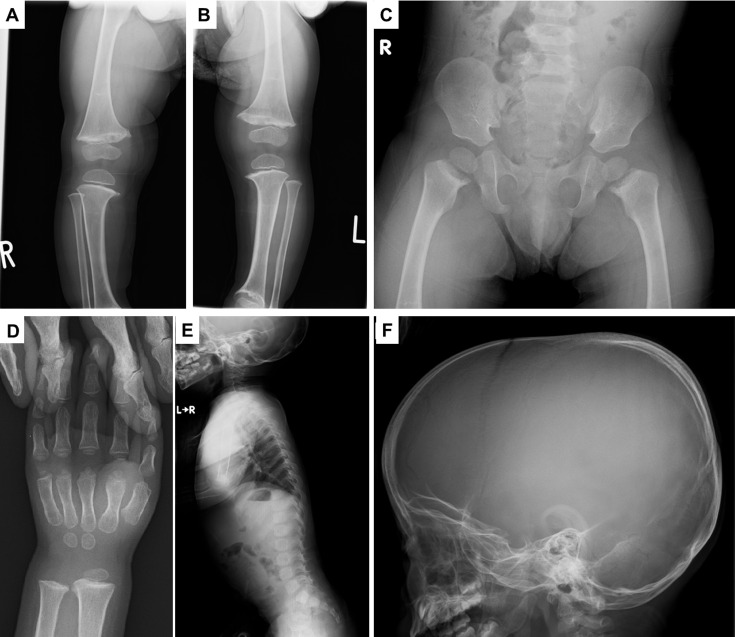

<i>COL10A1</i>-related metaphyseal dysplasia Schmid caused by the p.L644F variant in the <i>COL10A1</i> gene.